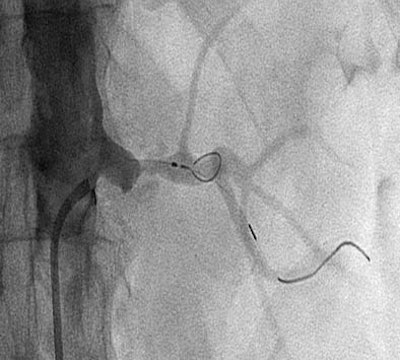

| A 71-year-old man with malignant hypertension and renal insufficiency. Angiogram shows inadequate diameter of basket and excessive length of wire distal to basket. Image republished with permission of the American Roentgen Ray Society, from AJR 2007; 188:1652-1658 by Adam D. Talenfeld, Ryan B. Schwope, Huntley J. Alper, Emil I. Cohen, and Robert A. Lookstein. |